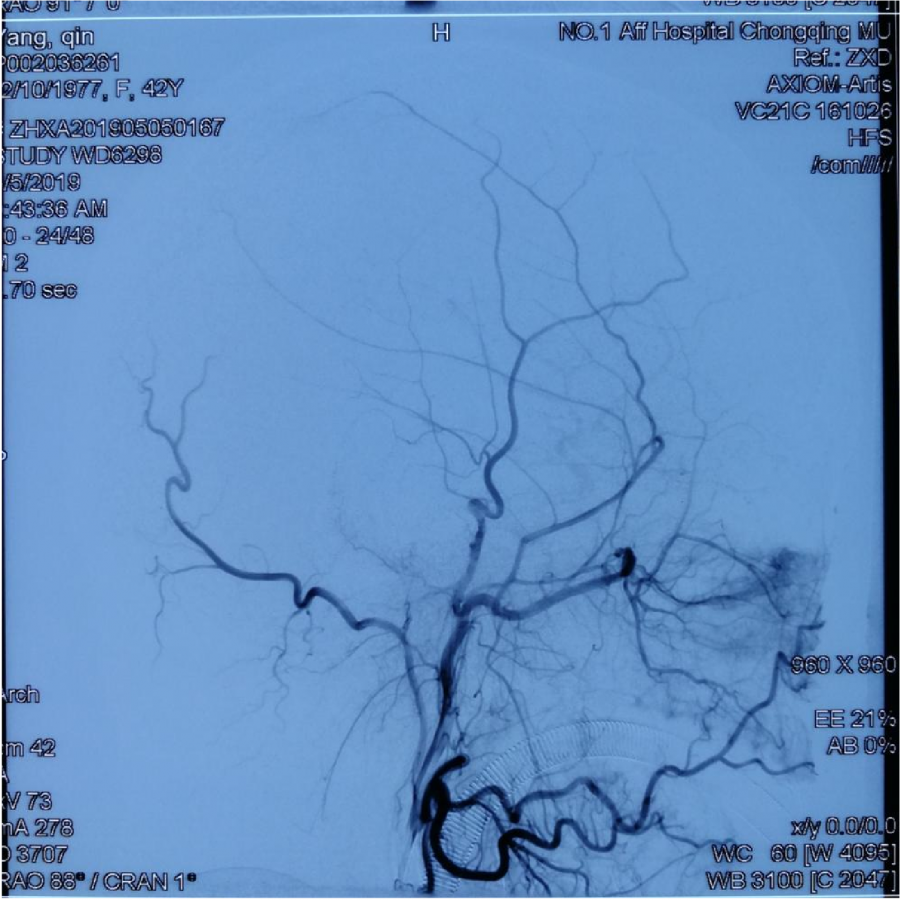

本次⼊院⾏DSA检查:PICA供⾎区有畸形⾎管团,引流到横窦